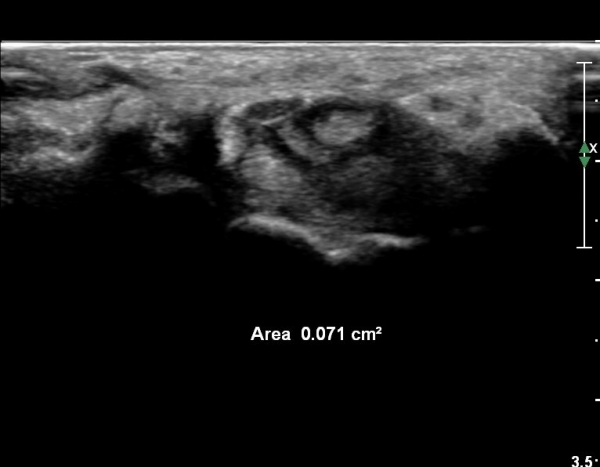

¼Õ¹Ù´Ú Ⱦ´Ü¸é°Ë»ç¿¡¼­ ÈûÁÙÀÇ ºñÈÄ¿Í ÈûÁÙ ÁÖÀ§ Ȱ¾×¸· ºñÈİ¡ °üÂûµÇ³ª

Á¤Áß½Å°æ ºÎÁ¾Àº °üÂûµÇ°í(»çÁø 5) µµÇ÷¯°Ë»ç¿¡¼­ ¼ö¾×Àú·ù°¡ °üÂûµÈ´Ù(»çÁø 6).